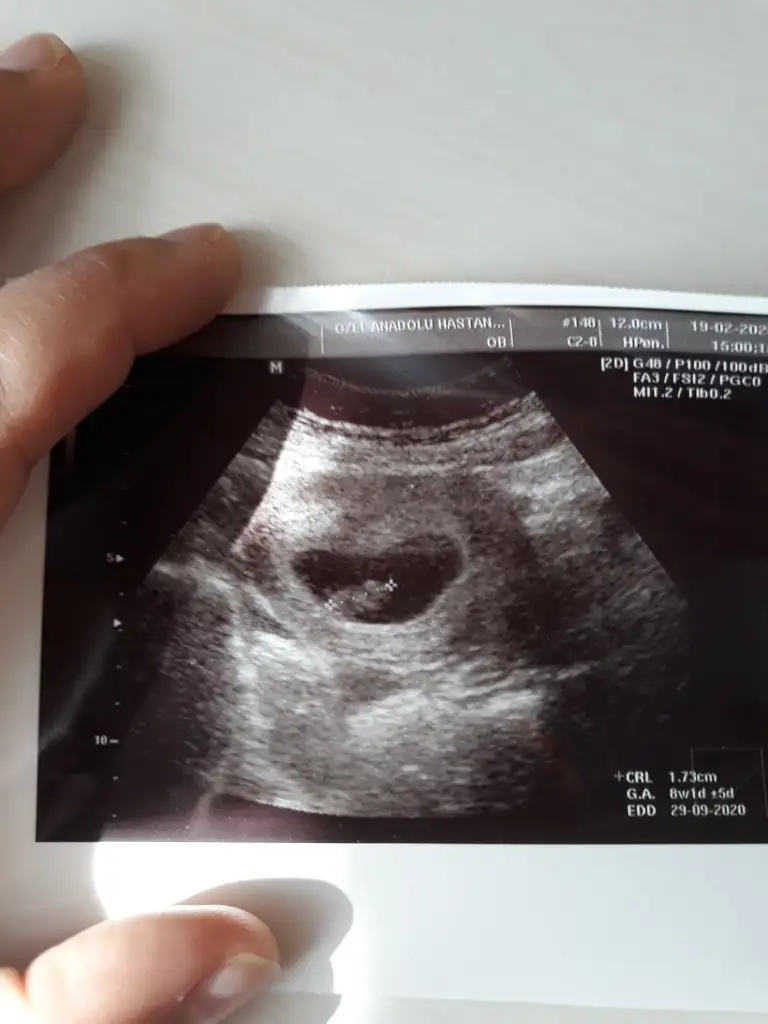

Arkadaşlar 10haftalik acama kizami erkek mi çok penziyo merak ediyorum

Eklentiler

• 15832202238201395352965.webp

15832202238201395352965.webp

29,1 KB · Görüntüleme: 288